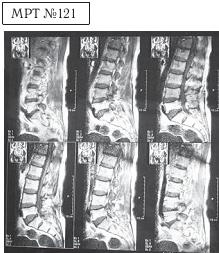

Фото № 19 На фото наблюдается описание снимка МРТ, сделанного после одного курса лечения методом вертеброревитологии. В нём отмечается умеренная дегенерация дисков (LIV—SI). LIV-LV, LV—SI; на уровне LIV-LV состояние после операции, незначительный эпидуральный послеоперационный фиброз. ![]() На МРТ № 121 общий снимок магнитно-резонансной томографии, на котором наблюдается полное отсутствие секвестрированной грыжи межпозвонкового диска в сегменте LIV-LV Состояние поясничного отдела позвоночника после одного курса лечения методом вертеброревитологии. Для детального ознакомления приведу увеличенные фрагменты данных снимков до и после лечения методом вертеброревитологии.